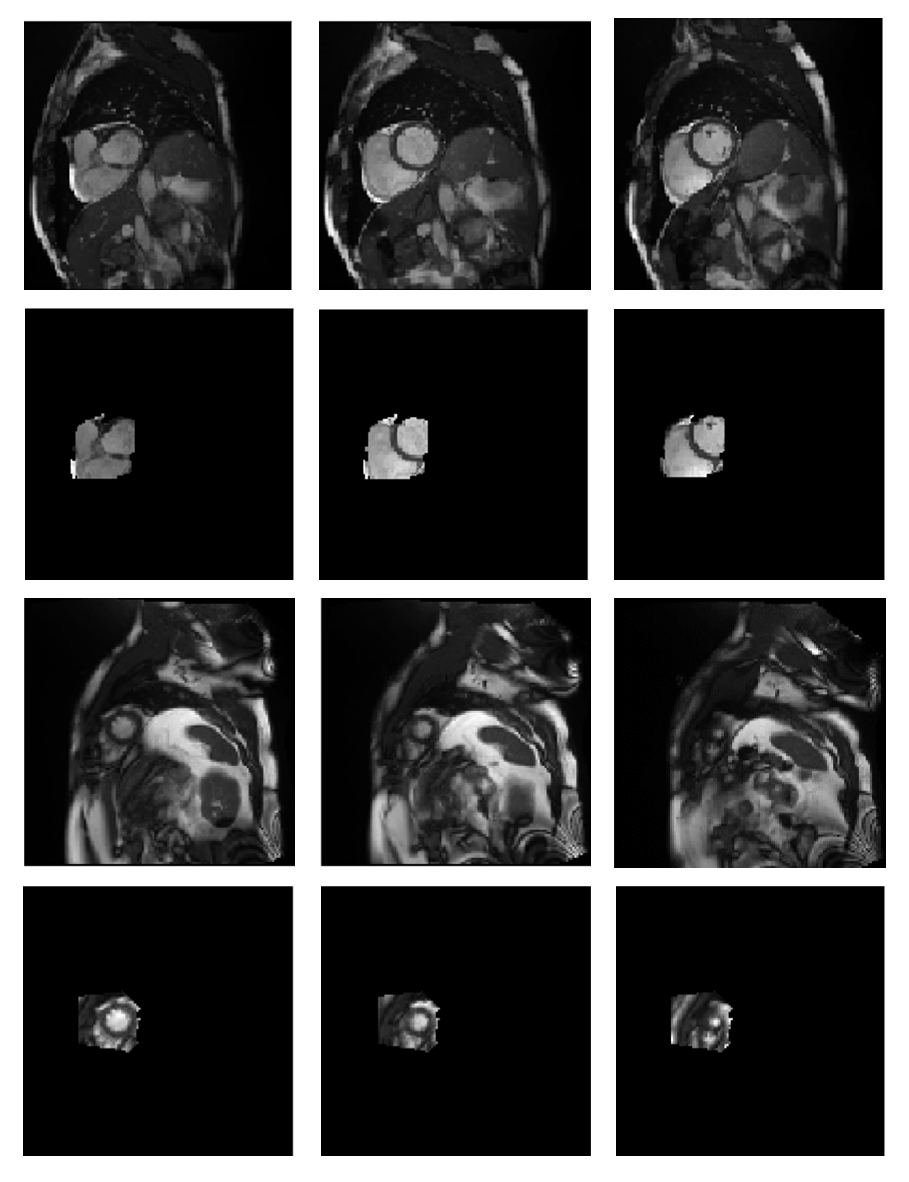

After training the 3D convolutional baseline model and performing the steps related to examining the interpretability of this model, and training the two U-Net models based on the most effective super-pixel obtained to identify the basal/apical slice, the proposed model can be used to extract the salient region of new stacks. If the most effective super-pixel in the prediction contains an area that includes the heart, it can be said that the baseline model has made a decision based on the correct region of the input stacks. An example of the most effective super-pixels in predicting basal/apical slice presence obtained during the interpretability control process of the baseline model is shown in Fig. 4. As shown in Fig. 4, the super-pixels that have had the most significant impact on classification include the area where the heart is visible. An experienced cardiologist subjectively monitored the baseline model’s interpretability control process results to ensure this issue. Accordingly, over 95% of the results contain areas that include the heart. This indicates that the baseline model is interpretable and works well.